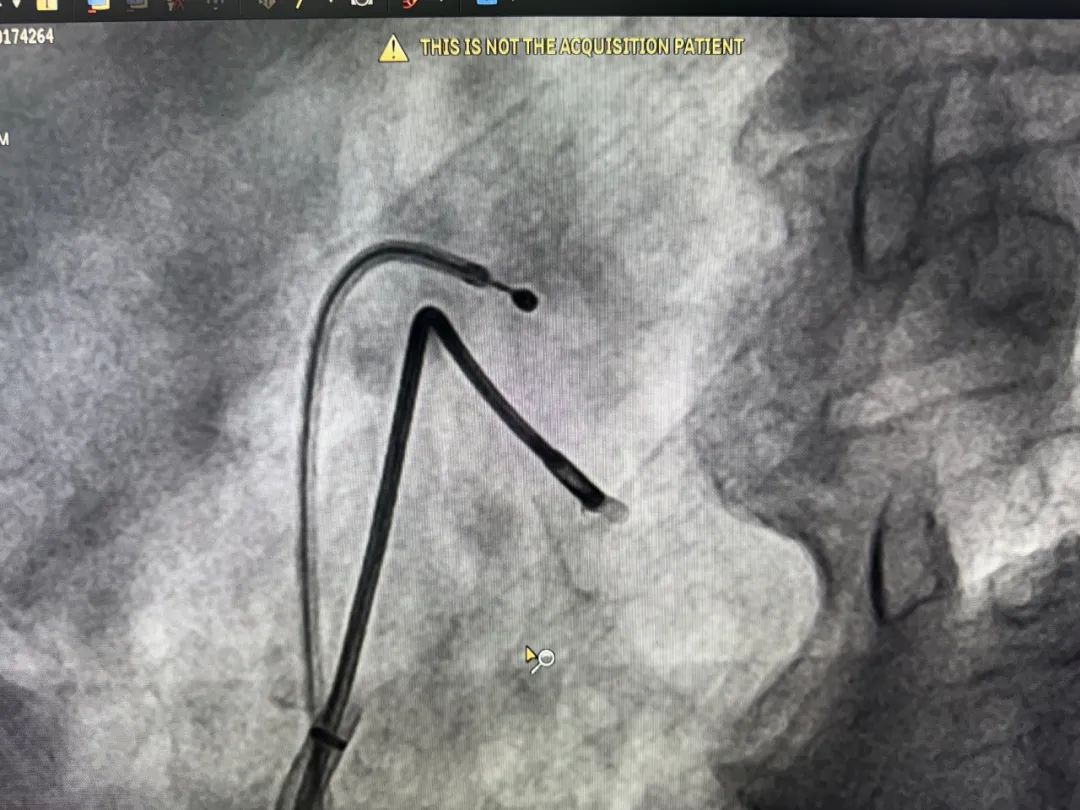

在开展多学科团队综合评估,并与患者家属进行充分沟通后,心血管内科主任任付先博士亲自带队,董发主任、郭磊主任协同参与。在介入导管室,刘岩团队积极配合,共同开展手术。术中经股静脉入路建立操作通道,通过数字减影血管造影(DSA)系统精准导航,使用专用活检钳依次获取右心室间隔部上段、中段及下段心肌组织样本。

心内膜心肌活检术中